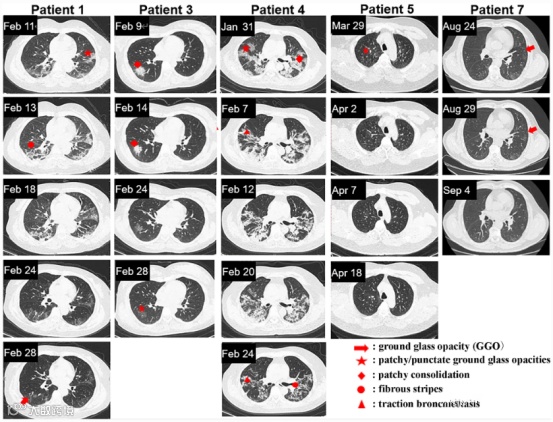

重度患者前后影像变化:

而未接受外泌体雾化治疗的重度患者,吸收肺病灶后仍然存在纤维脐带阴影。

▲左:重度患者,有外泌体雾化治疗

右:无外泌体雾化治疗的重度病例

▲患者1、3、4、5和7的胸部CT图像